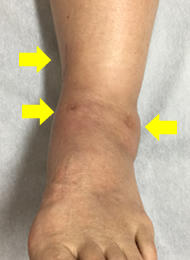

慢性足関節外側靭帯損傷

足関節の外側靭帯は、足関節の内返しの捻挫で最も損傷しやすい靭帯です。捻挫に対して適切な治療がなされなかったり、捻挫を繰り返したりすることで、慢性の外側靭帯の機能不全に陥ることが少なくありません。その場合、運動時の足関節の不安定感や疼痛、腫脹を生じます。

まず当院では、リハビリテーションによる回復を望めると判断した場合は、リハビリテーションによる保存的治療を行います。保存的に治療を行っても痛みが残る場合には、外側靱帯の縫縮術等を行っています。外側靱帯損傷に伴った軟骨の損傷を確認し、また手術における組織への侵襲を減らすため、可能な限り関節鏡で縫縮を行っています。損傷がひどい場合には再建術を行うこともあります。

![]() 内反ストレス単純レントゲン写真 |